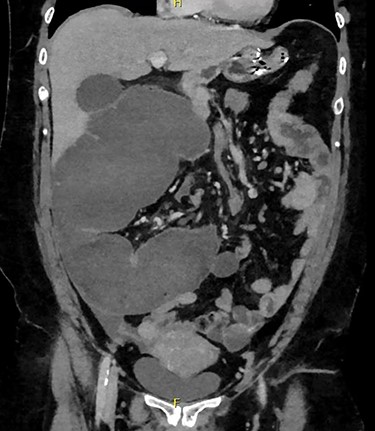

Admission blood tests were unremarkable. Abdominal X-ray showed non-specific signs of large bowel obstruction (Fig. 1). Computed tomography (CT) scan indicated unusual location of the caecum in the right upper quadrant along with gross distension up to 13 cm (Fig. 2), a whirling pattern of mesenteric vessels (Fig. 3) and a competent ileo-caecal valve. In context of her surgical history, these findings raised concern for a closed loop obstruction due to internal herniation.

On CT several particular features are diagnostic for caecal volvulus. The ‘bird’s beak’ sign shows the tapering of proximal and distal portions of bowels progressing towards the point of torsion [6, 7]. However, the most sensitive sign is a particular ‘whirl’ that is characteristic of mesenteric torsion and engorgement of blood vessels around a fixed point [8]. Evidence of this ‘whirl’ along with direction of the twist was 93% sensitive in the determination of caecal compared to sigmoid volvulus [8].